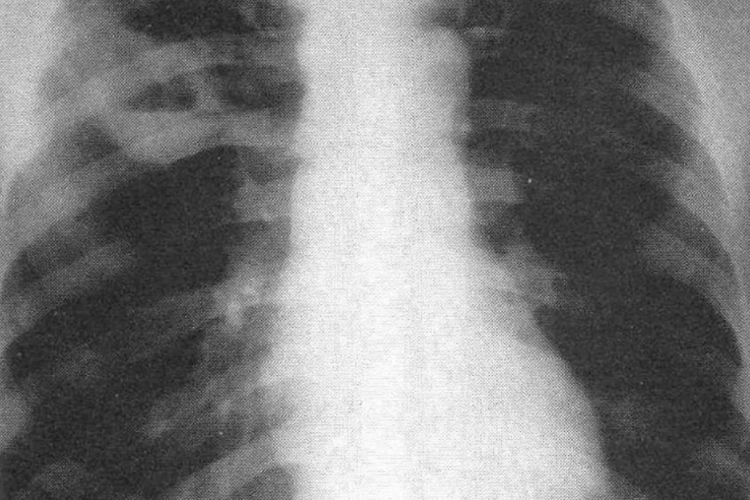

肺结核胸片通常指的是胸部X线检查,也是诊断结核病的重要方法,可以明确早期轻微的病变。肺结核的影像学特点是病变多发生在上叶的尖后段和下叶的背段,密度不均匀,边缘较为清楚,变化缓慢,易形成空洞和播散病灶。常采用正侧位胸片进行诊断,能将心影、肺门血管、纵膈等遮掩病变及中叶和舌叶的病灶显示清晰。

通常为了与其他胸部病变进行鉴别,还会进行CT检查,减少重叠影像,可以发现较为隐蔽的病变,从而减少微小病变的漏诊概率,相比于普通胸片可以显示更早期的微小粟粒结节,能清晰显示各型肺结核病变的特点和性质。